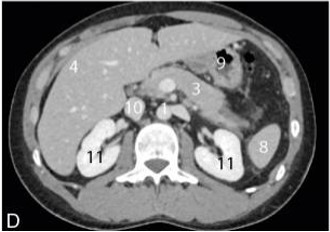

Je t'ai mis un schéma et une coupe axiale d'un scanner abdominal légendé pour que tu visualises au mieux :

Voici les légendes : 3 = Pancréas / 4 = Foie / 8 = Rate / 9 = Estomac

Ainsi sur cette incidence de coupe en T11 :

- Le foie parait latéralisé à gauche

- L'estomac parait latéralisé à droite

Pour la seconde partie concernant les rapports spléno-pancréatique :

on ne voit qu'une petite partie de la rate à cause de l'incidence de coupe, ainsi elle parait en avant (mais ce n'est pas le cas)

- En effet la rate est située

à l'extrémité de la queue pancréatique

- De plus, afin de bien comprendre il faut savoir que le pancréas est un organe profond (et plus particulièrement avec sa queue qui correspond à sa partie la plus profonde)

Ainsi

la rate est bien située en arrière du pancréas !